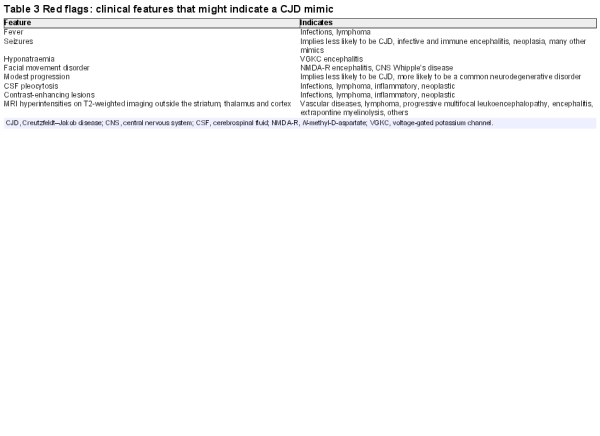

Mimics of CJD after initial investigation

Common neurodegenerative disorders

In over half of the mimics that the National Prion Clinic sees, the eventual diagnosis is another neurodegenerative disease. These conditions are much more prevalent than CJD and are also heterogeneous, with confusion only likely to occur with the very most rapidly progressing end of the spectrum of Alzheimer’s disease or dementia with Lewy bodies. Comorbidities, such as infection, leading to delirium, or drug changes are often a factor. Key features enabling recognition here are evidence from the witness account of pre-existing symptoms before the acute or subacute presentation. MR imaging evidence of focal or generalised atrophy or CSF abnormality of abeta or tau proteins are also instructive. The diagnosis becomes clear when patients stabilise or improve, which hardly ever happens in patients with CJD despite treatment of intercurrent infection. Vascular disease in the striatum, cortex or thalamus can also contribute to diagnostic confusion, because at first glance, this might suggest prion disease. Myoclonus, ataxia and motor signs can develop in common neurodegenerative diseases and can worsen with drug treatments, for example, tricyclics and myoclonus, antiepileptic drugs and ataxia, neuroleptics and dementia with Lewy bodies.

Although there are no specific disease-modifying therapies, accurate diagnosis of CJD can lead to meaningful management decisions about symptomatic therapies and choices for the patient and carers. All neurodegenerative disorders have Mendelian genetic causes, which (eg, in the case of C9orf72 expansion) can be associated with rapid progression and motor signs that bring CJD into the differential. The availability of gene panel diagnostics will identify an increasing proportion of cases with a specific genetic diagnosis.

We are particularly interested in potentially treatable mimics, which may be grouped into the following categories.

A wide range of bacterial, fungal and parasitic infections that can cause an RPD should be on a reference checklist (table 2) but have not caused diagnostic confusion with CJD at our clinic.

Toxic–metabolic syndromes

Most of these syndromes are picked up in the initial laboratory testing, which should include basic serum biochemistry, calcium, magnesium, glucose and thyroid function. It is important to emphasise the importance of Wernicke’s encephalopathy, an acute neurological disorder, precipitated by thiamine deficiency, characterised by the clinical triad of ophthalmoplegia, ataxia and confusion, which should be treated with urgent intravenous B vitamin replacement. Imaging features may partially overlap those of CJD. The encephalopathy associated with hepatic failure has mimicked CJD on a couple of occasions at our clinic, with the associated negative myoclonus (a sudden loss of muscle tone) in comatose patients mimicking the end stages of CJD. The detection of hyperammoninaemia either as part of rare genetic urea cycle disorders, drug therapy or liver failure can be crucial in the diagnosis of a toxic encephalopathy. In addition, a high signal in the lentiform nucleus on T1 MRI sequences due to manganese deposition strongly suggests hepatic encephalopathy.

Neoplastic and paraneoplastic conditions (other than limbic encephalitis)

The conditions hardest to distinguish are those with no or only subtle mass lesions on MRI. Typically, these include primary CNS lymphoma, carcinomatosis and intravascular lymphoma. In these cases, the imaging findings are usually the crucial diagnostic. Primary CNS lymphoma is usually associated with enhancing lesions in contact with CSF. Large-volume CSF sampling for cell analysis before a trial of corticosteroids may avoid brain biopsy. Serum tumour markers and whole-body imaging may also help. Intravascular (B-cell) lymphoma is a rare and notoriously difficult diagnosis. It leads to rapid cognitive decline, seizures, upper motor neurone signs and peripheral signs such as those of a neuropathy. Imaging findings overlap those of primary CNS vasculitis.

Vascular

Mimics relevant to other types of prion disease

Genetic and iatrogenic forms of prion disease often do not progress as rapidly as CJD and therefore have distinct differentials. A common phenotype of several inherited prion disease mutations is a modestly progressive (over the years) cerebellar ataxia, often with a distal leg sensory disturbance, absent ankle jerks and extensor plantar responses. Iatrogenic CJD also commonly presents with ataxia and normal or near-normal cognitive function and is slightly slower in progression than typical sporadic CJD. Other forms of inherited prion disease have pure cognitive presentations, often with behavioural disturbance and are mistaken for the frontal variant of Alzheimer’s disease, Huntington’s disease (as there is an autosomal dominant family history) or frontotemporal dementia.